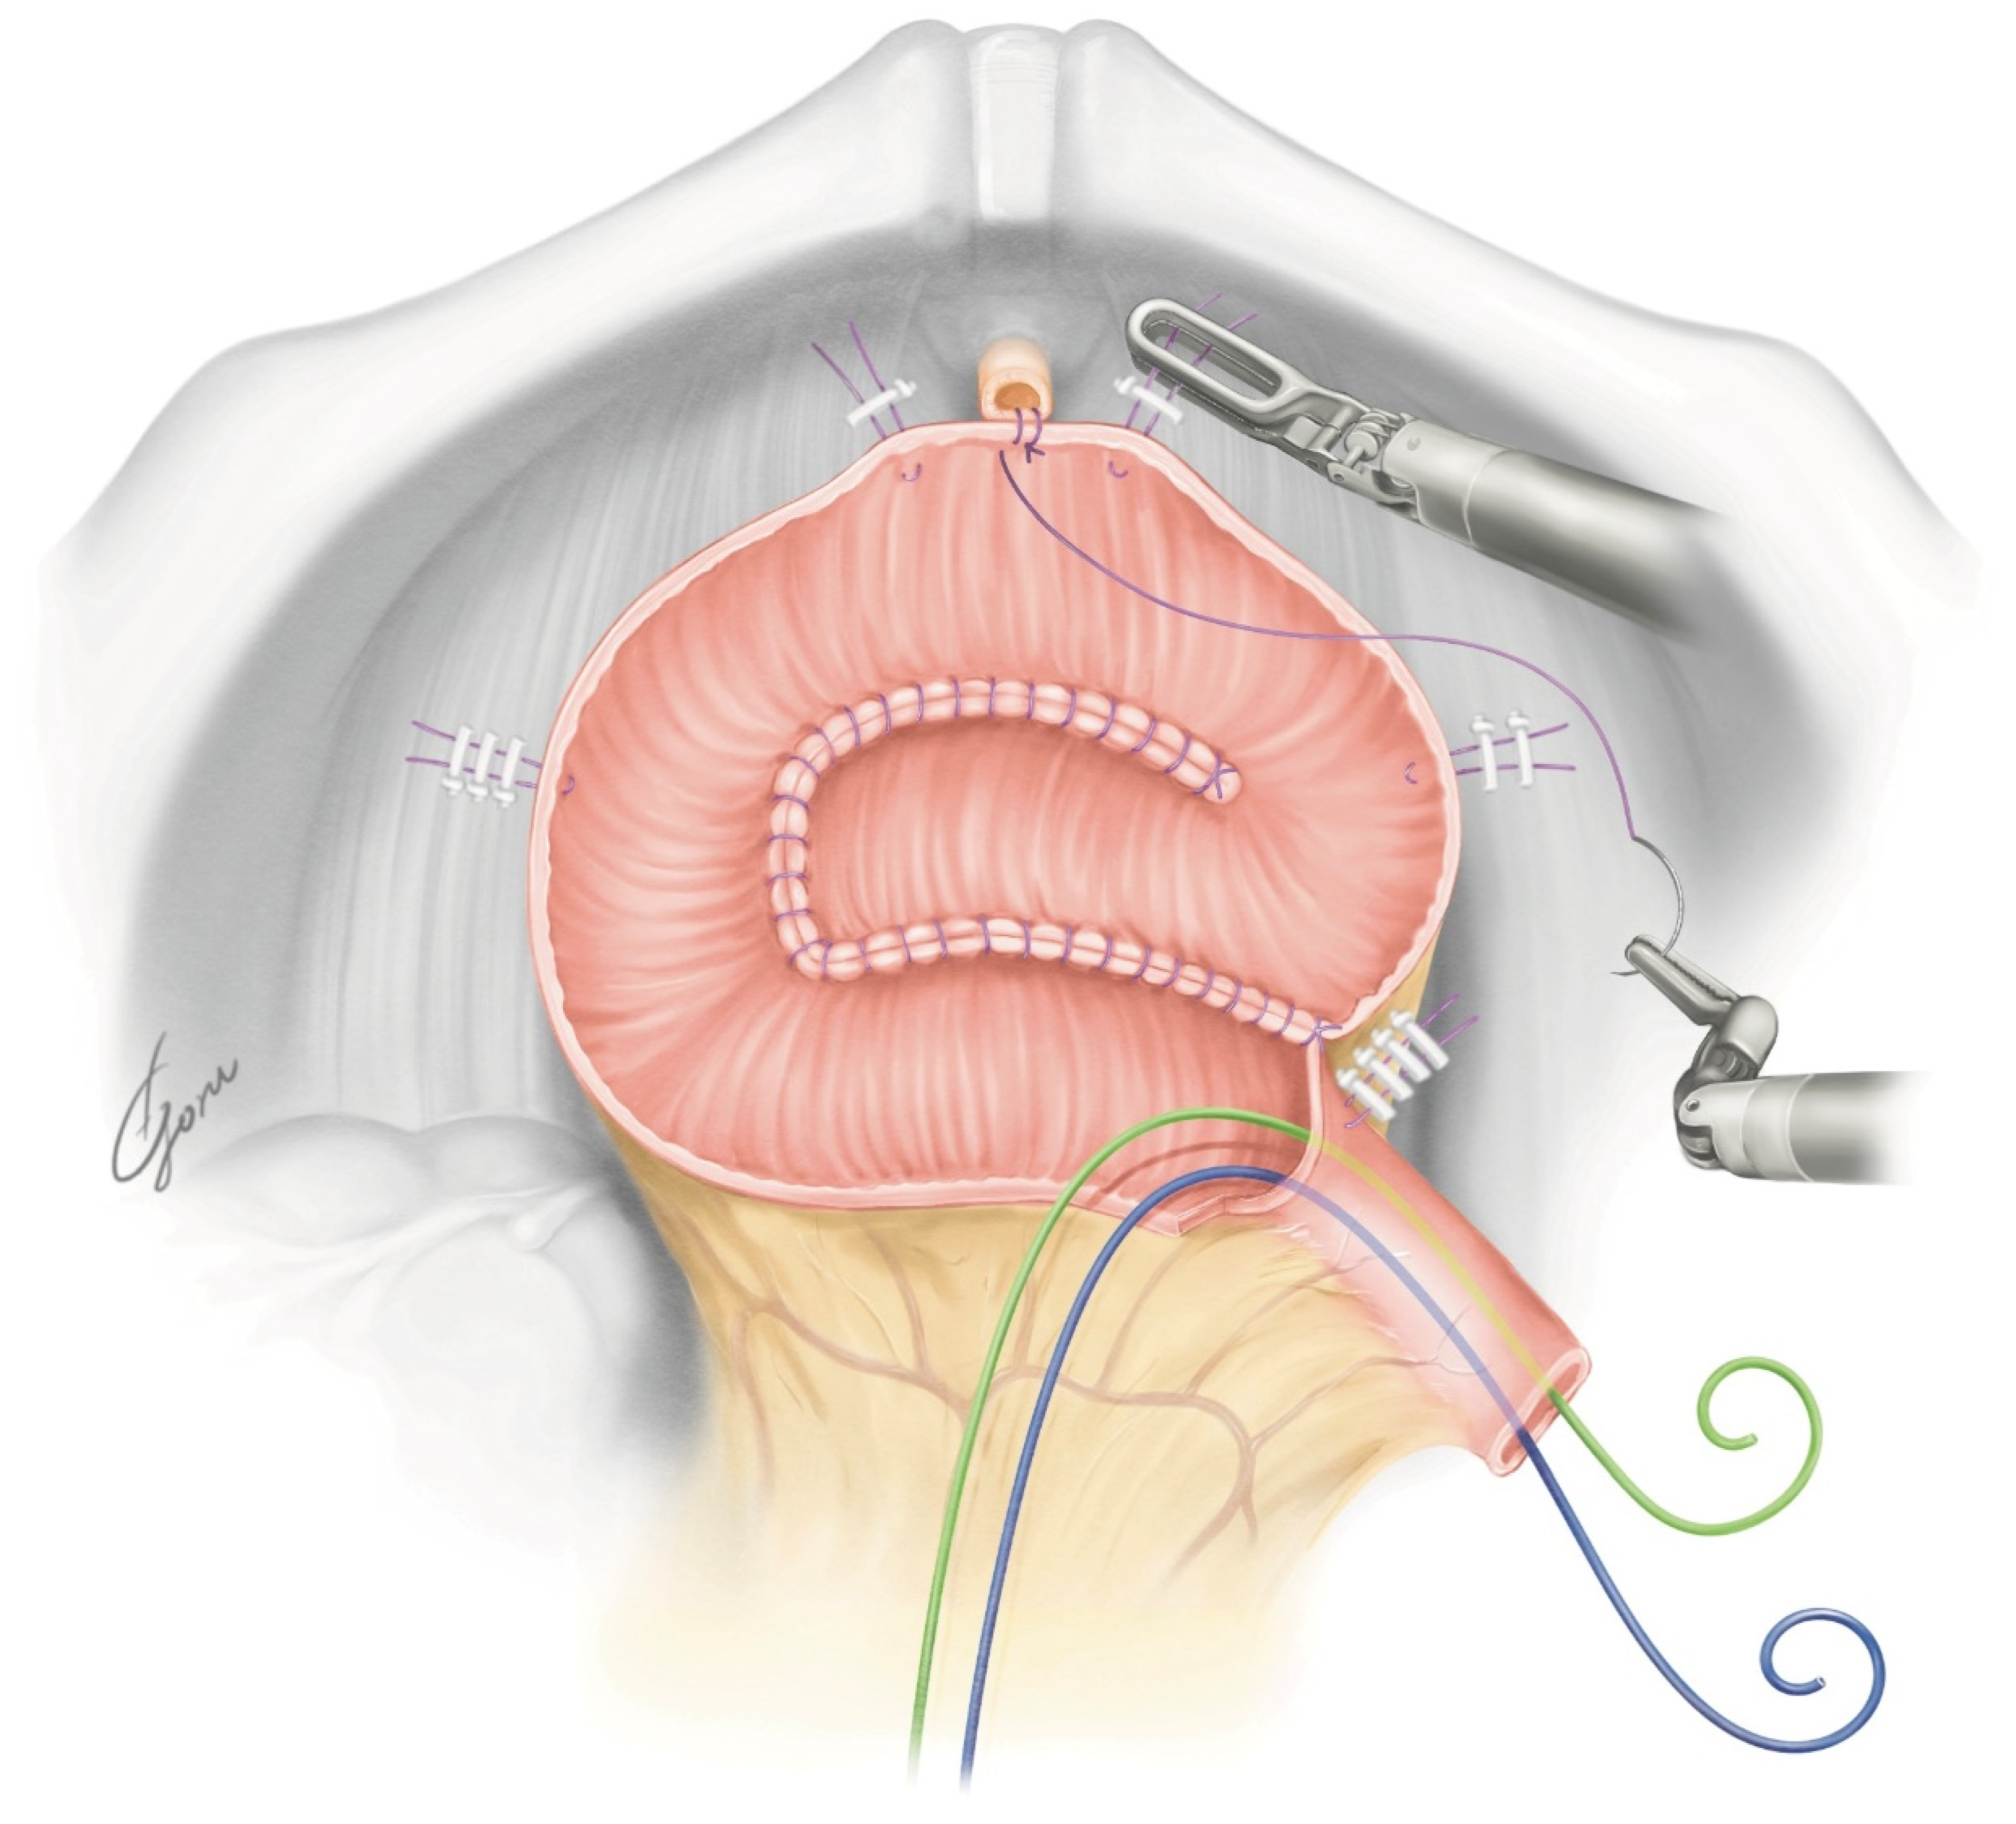

The robot was redocked head-down at 10–12 degrees. The right supporting suture of the posterior plate was grasped with 4th arm forceps and the posterior plate was mobilized to the pelvic floor. A circumferential urethra–ileal anastomosis was performed using 3-0 VLoc sutures, similar to a robot-assisted radical prostatectomy (RARP) (Figure 3). The advantage of performing a circumferential anastomosis after creating a posterior plate is the visibility of the urethra during an anastomosis. If an opening is made and a urethral anastomosis is performed before detubularization, the part to be anastomosed may be difficult to visualize in Asian individuals with narrow pelvises. The anterior wall of the NB was continuously sutured so it was water-tight and tension-free using 3-0 VLoc sutures from the left and right toward the center. Via this manipulation, a folded structure could be obtained. A 20Fr Foley catheter was inserted and inflated with 20cc water when the anterior wall was half-closed. A bilateral 6Fr ureteral stent was passed through the anterior wall into the abdominal wall and inserted into each ureter using a guidewire. The remaining anterior wall was closured. Figure 4 shows the schema of the ileal NB created via our method.

Figure 3.

The shape of the posterior plate when pulled toward the urethra.

Figure 4.

The schema of the NB created using our method.